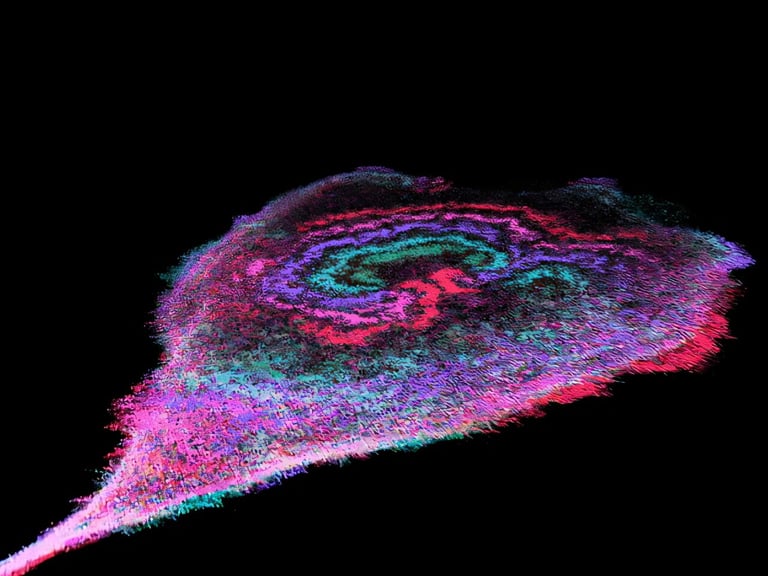

Recent research has uncovered that in aggressive cancer cells, such as those in breast, pancreatic, lung, colon, and liver cancers, glycolytic enzymes form organized waves on the cell membrane, a phenomenon absent in normal cells.

These enzyme-driven waves are associated with increased ATP production, especially in more aggressive cancer subtypes, suggesting a link between wave activity and cancer severity.

The waves are generated by enzymes involved in glycolysis, the glucose-based energy process, and are more prevalent in highly aggressive cancer cells, highlighting a potential universal feature across multiple cancer types.

This discovery indicates that energy waves help coordinate cellular behavior with metabolic needs, allowing cancer cells to rapidly reorganize their energy infrastructure in response to activity demands.

The wave activity offers a mechanical explanation for the Warburg effect, facilitating quick energy production necessary for processes like cell movement, nutrient uptake, and membrane reshaping.

Scientists at Johns Hopkins Medicine have identified that rhythmic enzyme activity creates energy-generating waves on cancer cell membranes, which may fuel tumor growth and metastasis.